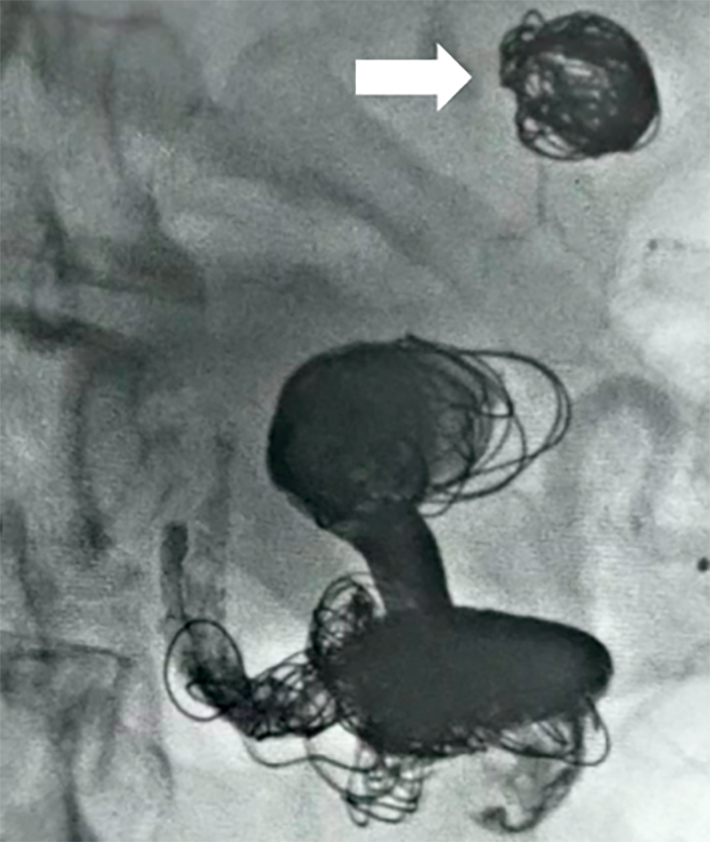

脾动脉瘤是第三种最常见的腹内动脉瘤,也是最常见的内脏动脉瘤。门静脉高压是这类动脉瘤发病的重要危险因素。我们报告了一例 52 岁的白人女性患者,她患有多发性脾动脉瘤和脾功能亢进,继发于门静脉高压症和肝硬化。腹部血管造影发现了六个脾动脉瘤。在这种情况下,安排了一次血管内介入治疗,使用控释线圈和Onyx™栓塞剂进行栓塞。三个最大的动脉瘤得到了治疗。对照血管造影显示动脉瘤排除良好。因此,考虑到患者的合并症和血液疾病,血管内技术被证明是一个不错的选择。在这个病例中,手术非常成功。没有出现即刻或长期并发症。患者恢复良好,目前正在接受临床随访。

Aneurysms of the splenic artery are the third most common type of intra-abdominal aneurysms and the most common type of visceral aneurysms. Portal hypertension is a significant risk factor for development of these aneurysms. We report the case of a white, female, 52-year-old patient with multiple splenic artery aneurysms and hypersplenism secondary to portal hypertension and cirrhosis. Abdominal angiotomography identified six splenic aneurysms. In this scenario, an endovascular intervention was scheduled to conduct embolization using controlled release coils and Onyx™ embolization agent. The three largest aneurysms were treated. Control angiographs showed good exclusion of the aneurysms. The endovascular technique therefore proved to be a good choice considering the patient's comorbidities and blood disorders. In this case, the procedure was successful. There were no immediate or long-term complications. The patient recovered well and is in clinical follow-up.